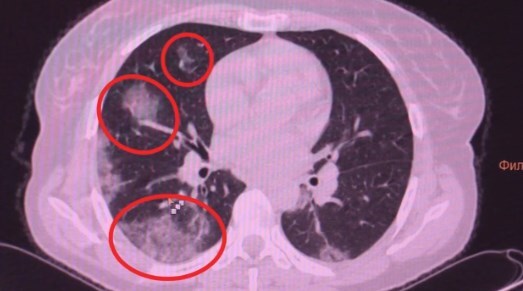

Японские и американские врачи обнаружили патологию у людей, которые переболели коронавирусом без симптомов.

У некоторых пациентов происходят изменения в легких.

Отмечается, что человек чувствует себя нормально, но коронавирус повреждает легочную ткань, на которой образуются уплотнения.

Врач-рентгенолог "Медико-хирургического центра на Пресне" Людмила Леонова пояснила, что воспаленная зона в легких начинает фиброзироваться (фиброз – уплотнение легочной ткани).

По ее словам, если болезнь протекает в легкой форме, то фиброз со временем проходит. Однако в тяжелой форме он чаще всего остается, учитывая возрастные показатели населения.